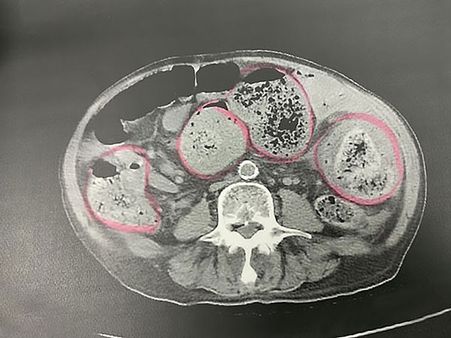

They Discovered His Intestines Were Full Of Faeces

The medics were shocked to find out that the man was suffering from extreme constipation state. They discovered that his intestines were full of faeces!

He Was Operated

The man was immediately taken for a surgery. When the medics started the surgery, they found that some parts of his intestine had already necrotised and turned black, which means that the tissues there had died.

They Removed 30 cm Of His Intestine!

According to the reports, the surgeon had to remove 30 cm of his intestine since the tissues of his intestine had already died and the old man had to be hospitalised for half a month before he made a complete recovery.